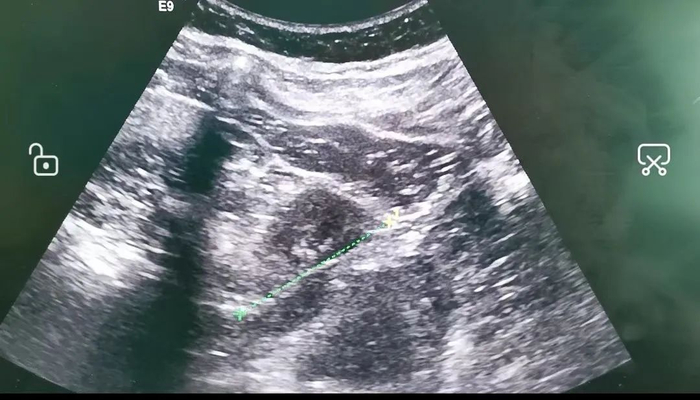

张先生长期以来无故反复腹痛,近来更是出现了血尿症状,在医院行腹部CT检查提示:十二指肠及右肾部长条状高密度影,考虑有异物贯穿两个脏器可能。

手术当天,麻醉科主治医师聂瑞霞实施气管插管全麻后,超声科主任医师马力运用彩超监测,消化内镜中心主治医师叶丽芳透过高倍显微内镜,精准定位异物位置,巧妙地将异物“牙签”取出,并在异物的穿刺口予以夹闭。过程中超声监测异物所在区域没有出血外渗等情况。

手术取出一只长6.5厘米的牙签,一端已被消化液腐蚀。